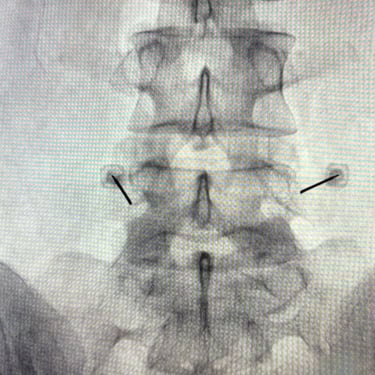

La discopatía lumbar y la espondiloartrosis forman parte del proceso degenerativo de la columna vertebral y pueden generar dolor lumbar persistente, irradiación hacia miembros inferiores y limitación funcional. Diversos estudios clínicos han demostrado que el bloqueo lumbar selectivo es una herramienta diagnóstica y terapéutica útil en estos pacientes. El procedimiento consiste en la infiltración guiada por fluoroscopía o ecografía de anestésicos locales y corticoides cerca de la raíz nerviosa o articulación facetaria comprometida. Esta técnica permite confirmar la fuente del dolor y disminuir la inflamación neural. En pacientes seleccionados, puede mejorar significativamente la calidad de vida y retrasar o evitar tratamientos quirúrgicos.